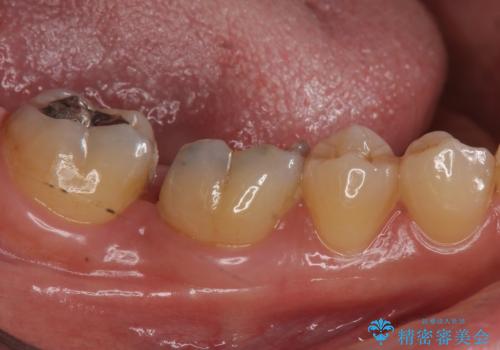

もう一つ奥の歯に関してもセラミックにやり替えたいとのことでしたので、こちらはインレーでの治療を行いました。

- 右下6:仮歯+セラミッククラウン/11,000円+110,000円 右下7:セラミックインレー/77,000円費用は治療当時の料金となります